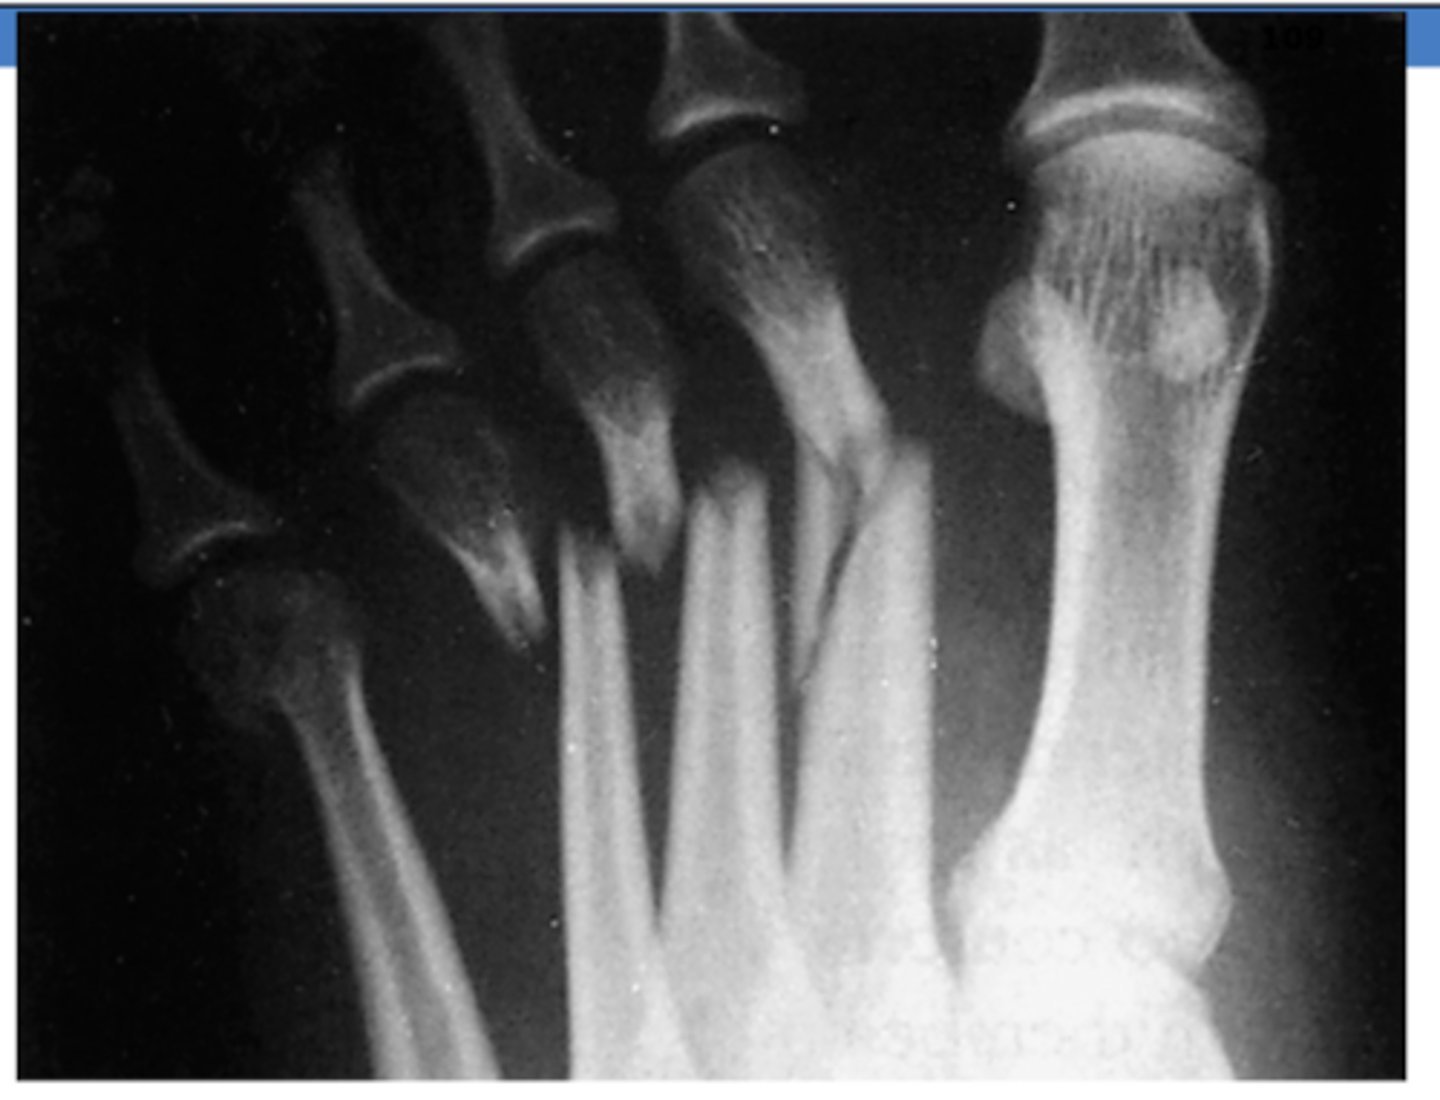

What is fractured in the following XR?

metatarsals

Fracture of the 5th metatarsal is also known as what?

Jone's fracture